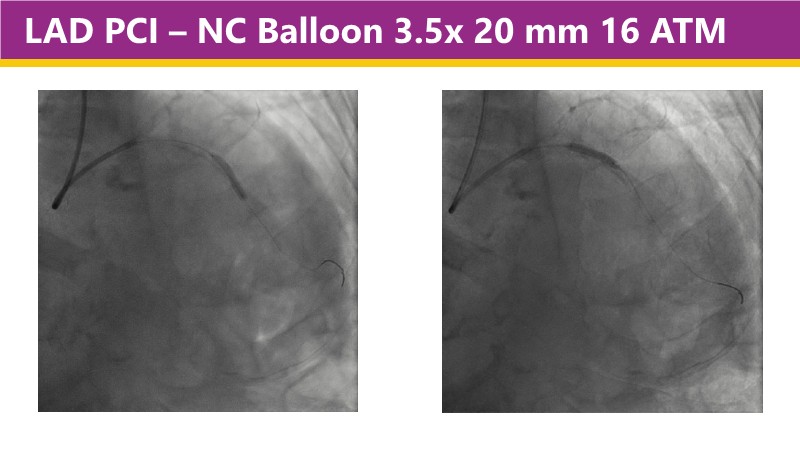

Learn how this technology works, review the supporting evidence, and follow step-by-step case examples demonstrating optimal stent expansion and an efficient calcium modification workflow in daily practice.